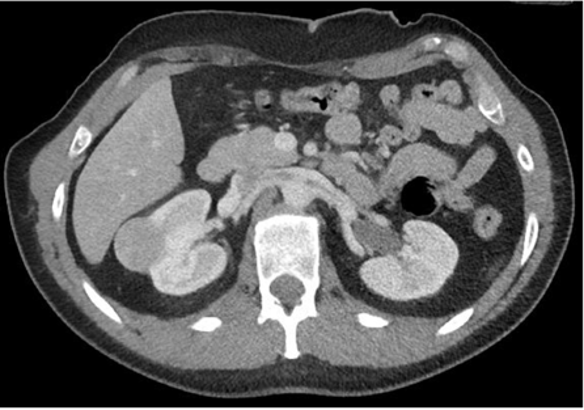

Q

Hvilken CT-projektion er vist?

A

• Aksial (Transversal)